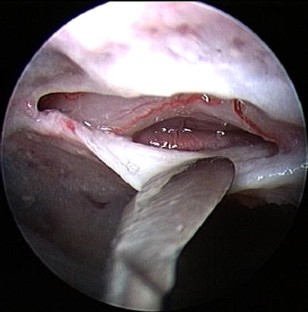

Fig. 1